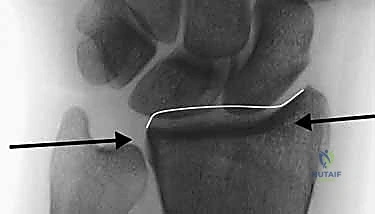

- الحافة الأمامية (الراحية) للوجه الهلالي (Volar Lunate Facet):

هذا الهيكل التشريحي الصغير هو سطح رئيسي يتحمل الأحمال في الغضروف المفصلي، حيث ينقل القوة من اليد إلى الساعد. استقراره بالغ الأهمية لمنع انزلاق عظام الرسغ. عادة ما يواجه الجراحون نمطين خطيرين من عدم الاستقرار هنا:- نمط عدم الاستقرار الأمامي (Volar Instability): يتميز بتقصير وانزياح أمامي للحافة، مما قد يؤدي إلى خلع جزئي (Subluxation) لعظام الرسغ (خاصة العظم الهلالي - Lunate). هذا يضر بقدرة تحمل الوزن ويؤثر بشكل كبير على قوة القبضة.

- نمط عدم الاستقرار المحوري (Axial Instability): يؤدي الانضغاط المحوري القوي إلى دفع الحافة الأمامية نحو الانثناء الظهري. غالباً ما يؤدي هذا إلى خلع جزئي ظهري لعظام الرسغ، مما يعطل ميكانيكا المفصل بالكامل ويسبب ألماً مبرحاً.

- التصوير المقطعي المحوسب (CT Scan) مع إعادة البناء ثلاثي الأبعاد:

هذا هو المعيار الذهبي الذي يعتمده الدكتور هطيف لجميع كسور المفصل المعقدة. تتيح الأشعة المقطعية رؤية كل شظية عظمية بوضوح تام، وتحديد حجمها، وموقعها، ودرجة تفتت السطح المفصلي بدقة ملليمترية. من خلال إعادة البناء ثلاثي الأبعاد (3D Reconstruction)، يمكن للدكتور هطيف "رؤية" الكسر من جميع الزوايا قبل فتح الجلد، مما يسمح له باختيار الغرسات (الصفائح والمسامير) الدقيقة لكل شظية وتحديد المداخل الجراحية المثلى.